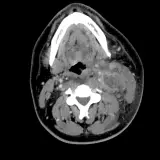

Over 2,100 interactive radiology cases, curated by radiologists for your level of training. Scroll, window, and view cases full screen โ€” just like on PACS. Click linked findings in each writeup to jump straight to them on the image. Cases include sample reports, a focused discussion section, original illustrations, and videos.

Casi completamente interattivi con gli strumenti che ti aspetti su un PACS: scroll, windowing, zoom, pan, misurazioni, ROI e modalitร  a schermo intero.

Annotazioni dettagliate evidenziano i reperti chiave direttamente sui casi. Clicca sui reperti collegati nella descrizione del caso per saltare alla loro esatta posizione sullo scan.